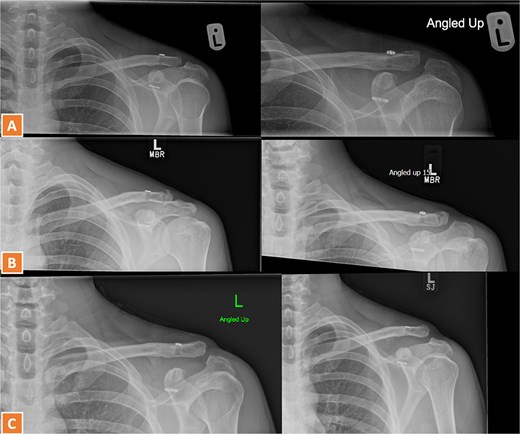

A 30-year-old male presented with an unstable lateral clavicle fracture and skin tenting after a rugby injury. Imaging revealed a Neer type IV equivalent fracture (Fig. 3). He underwent open reduction and internal fixation with coracoid exposure and TightRope placement, reinforced with fiber-wire. Postoperative recovery included sling immobilization followed by pendular exercises. Despite delayed radiological union, he achieved full range of motion and strength by three months, with only mild, asymptomatic clavicular prominence. He returned to physically demanding work without restrictions, and final imaging confirmed union (Fig. 4A–C).

Radiographs of second case showing a displaced lateral end clavicle fracture with deformity and dorsal displacement.

(A–C) Radiographs showing complete healing of the second case and union at 3, 6, and 12 months post-operatively.